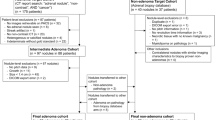

In total, we discovered 195 indeterminate adrenal masses meeting the inclusion criteria in 172 subjects in the given time period. Out of these, 32 masses in 31 subjects were excluded because follow-up imaging examination or histology was missing and thus it was impossible to determine the diagnostic conclusion (Fig. 1).

Retrospective analysis was performed on 163 masses in 141 subjects. The study group included 68 males and 73 females; the age range was 18–89 years and the mean age was 61.9 years. The adrenal masses were located on the right side in 45 cases and on the left side in 74 cases and were bilateral in 22 cases.

The study group included 83 lipid-poor adenomas, out of which 12 were confirmed by histology and 71 by stable size during a follow-up after at least 6 months. The remaining adrenal masses were non-adenomas (21 pheochromocytomas, 55 metastases and four adrenocortical carcinomas), out of which 36 were confirmed by histology (11 metastases and all the pheochromocytomas and carcinomas), and 44 metastases were confirmed by the rapid growth of the adrenal mass in subjects with known malignancy.